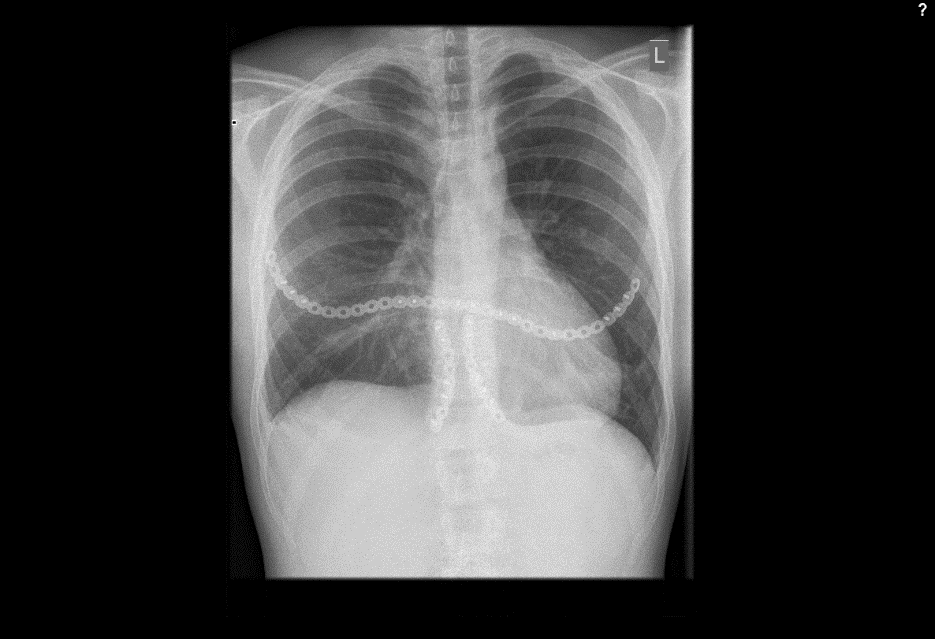

Fall from 4-meter height

Mechanism of injury: An 81 year old woman fell onto her back from a height of 4 meters. (Fig 6a-d) She sustained a multiple sternal fracture concomitant with a fracture of the 5th thoracic vertebra resulting in an unstable injury of the trunk. Fortunately she did not show any neurologic deficit or paraplegia.

Diagnosis: Complex sternal fracture with multidirectional instability (longitudinal fracture of the manubrium, transverse fracture involving 3 levels of manubrium and corpus sterni) Concomitant to this was a fracture of the 5th thoracic vertebra (AOB2.1).

Treatment: The sternal fracture has been managed by open-reduction and internal fixation with a locked plate osteosynthesis (MatrixRIB, I-Plate) through an anterior approach in the mid-line. b The thoracic spine has been managed employing dorsal instrumentation (internal fixator th4-th6).

Post-operative outcome: The wounds and bone healed uneventfully. Breathing was possible spontaneously without any restrictions. The patient reported on a significant reduction of the pain immediately after the operative procedure. Mobilization on the ward started on the first day after the procedure. No complications such as secondary failure, non-unions, pain or deformity of the chest wall could be seen during the follow up examinations of 6 and 12 weeks and 6 and 12 months.